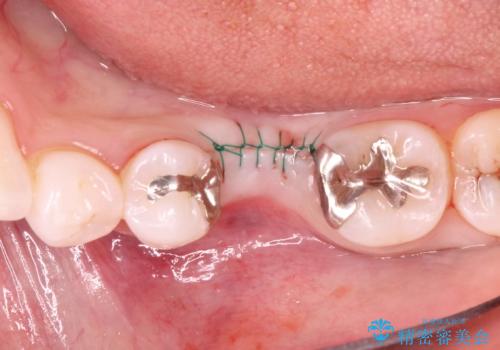

- 治療計画

- 保存不可能な歯の抜歯後、待時にてインプラントを埋入、2回法にて咬合回復を計画した。

- 外科手術のため、術後に痛みや腫れ、違和感を伴います